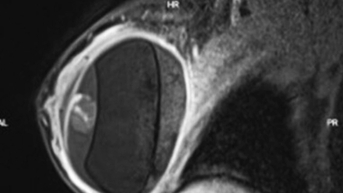

Dưới đây là một trường hợp chị khách Việt kiều từng nâng ngực 2 lần. Lần 1 đặt túi cách đây 10 năm, đã từng tháo túi ngực 1 lần. Sau đó, lần 2 tiếp tục đặt túi với vị trí đường mổ bờ ngoài và hiện tại gặp tình trạng ngực bị thông khe, khoang đặt túi rộng dẫn đến túi ngực đổ bên ngoài và sẹo lồi đường mổ cũ.

Được sự giới thiệu chị đến tư vấn và thực hiện phẫu thuật tháo túi ngực và tạo hình ngực, điều chỉnh ngực bị thông khe và đặt túi mới. Trong quá trình phẫu thuật lại bác sĩ rạch da đường chân núm vú lấy túi ngực nhám cũ Establish Ment Sz 355cc, khâu và tạo hình lại khoang ngực phù hợp với size túi mới, cắt sẹo xấu khâu thẩm mỹ.